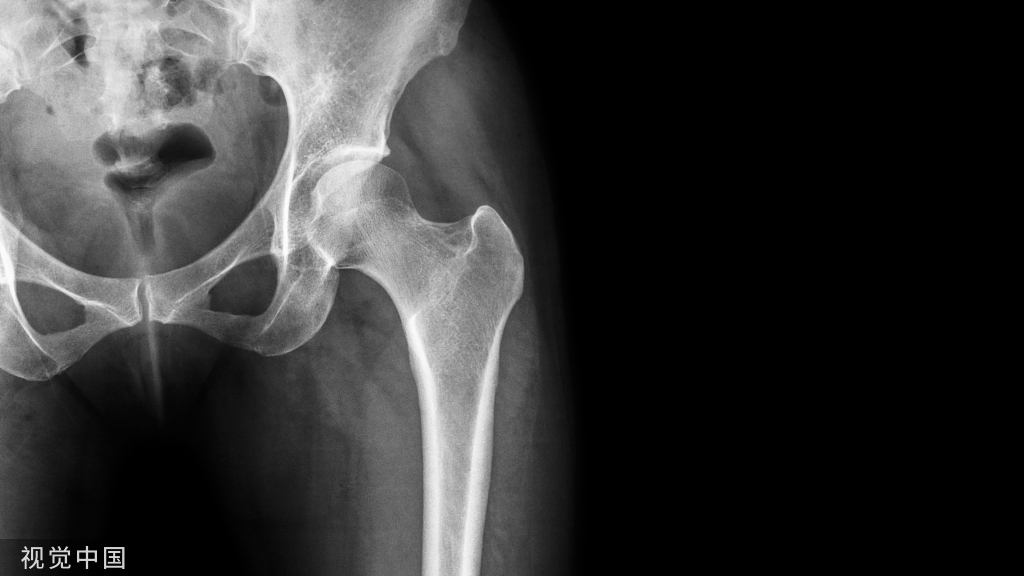

连续49名股骨转子周围骨折的老年患者被纳入研究设计(证据等级2)。研究组25名患者接受了骨水泥强化髓内钉(PFNA)(CA组),而对照组24名患者接受了相同的骨折固定术而没有骨水泥强化(NCA组)。术后第五天,所有患者都参加了使用鞋垫力传感器测量负荷率的步态分析(loadsol,Novel,慕尼黑,德国)。

[Methods: Forty-nine orthogeriatric patients with pertrochanteric fractures were enrolled consecutively in a maximum care hospital in a pre–post study design (level of evidence 2). A study group of 25 patients received nailing (PFNA) with additional cement augmentation (CA group), whereas the control group of 24 patients received the same fracture fixation without cement augmentation (NCA Group). All patients participated in a gait analysis using an insole force sensor to measure the loading rate (loadsol®, Novel, Munich, Germany) on the fifth postoperative day.]

NCA组的平均年龄为75.88岁(标准差:9.62),CA组的平均年龄为81.44岁(标准差:7.77)。两组中最常见的骨折类型为股骨粗隆间骨折(NCA: n=20,CA: n=21)两组在ASA分级方面(NCA:2.67;CA: 2.68)和术后Parker活动度评分(NCA:2.67;CA: 2.68)上无明显差异。接受骨水泥强化的患者在术后步态分析中显示出显著(p=0.004)的高负荷率。CA组的负荷率为58.12%(标准差为14.50),而非骨水泥PFNA组的负荷率为43.90%(标准差为18.34)。

[Results: The NCA group showed a mean age of 75,88 years (SD ± 9.62), the CA a mean age of 81,44 years (SD ± 7.77). The most common fracture type was a pertrochanteric fracture in both groups (NCA: n=20, CA: n=21) Both groups showed no differences with regards to the ASA (NCA: 2.67; CA: 2.68) score and the postoperative Parker Mobility Score (NCA: 2.67; CA: 2.68). Patients who received cement augmentation showed a significant (p=0.004) higher loading rate in the postoperative gait analysis. The CA group showed a loading rate of 58.12% (SD ± 14.50) compared to the uncemented PFNA group with 43.90% (SD ± 18.34).]